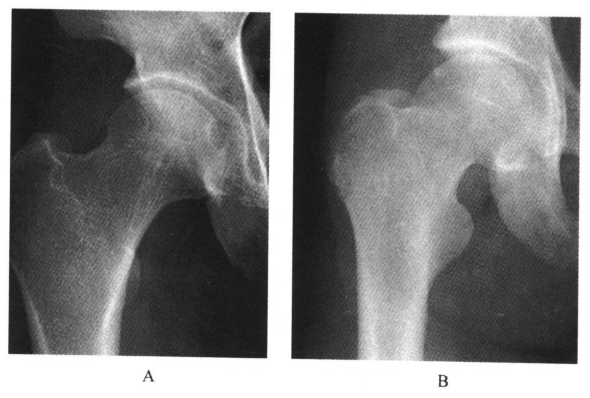

1.股骨头圆韧带窝在髋关节正位片上表现为股骨顶部小半圆形骨质缺损,在旋转屈曲位时表现为股骨头中心部有小空洞(图1)。

图1 正常股骨头圆韧带窝A.韧带窝明显,极似骨缺损;B.转动体位后骨质正常